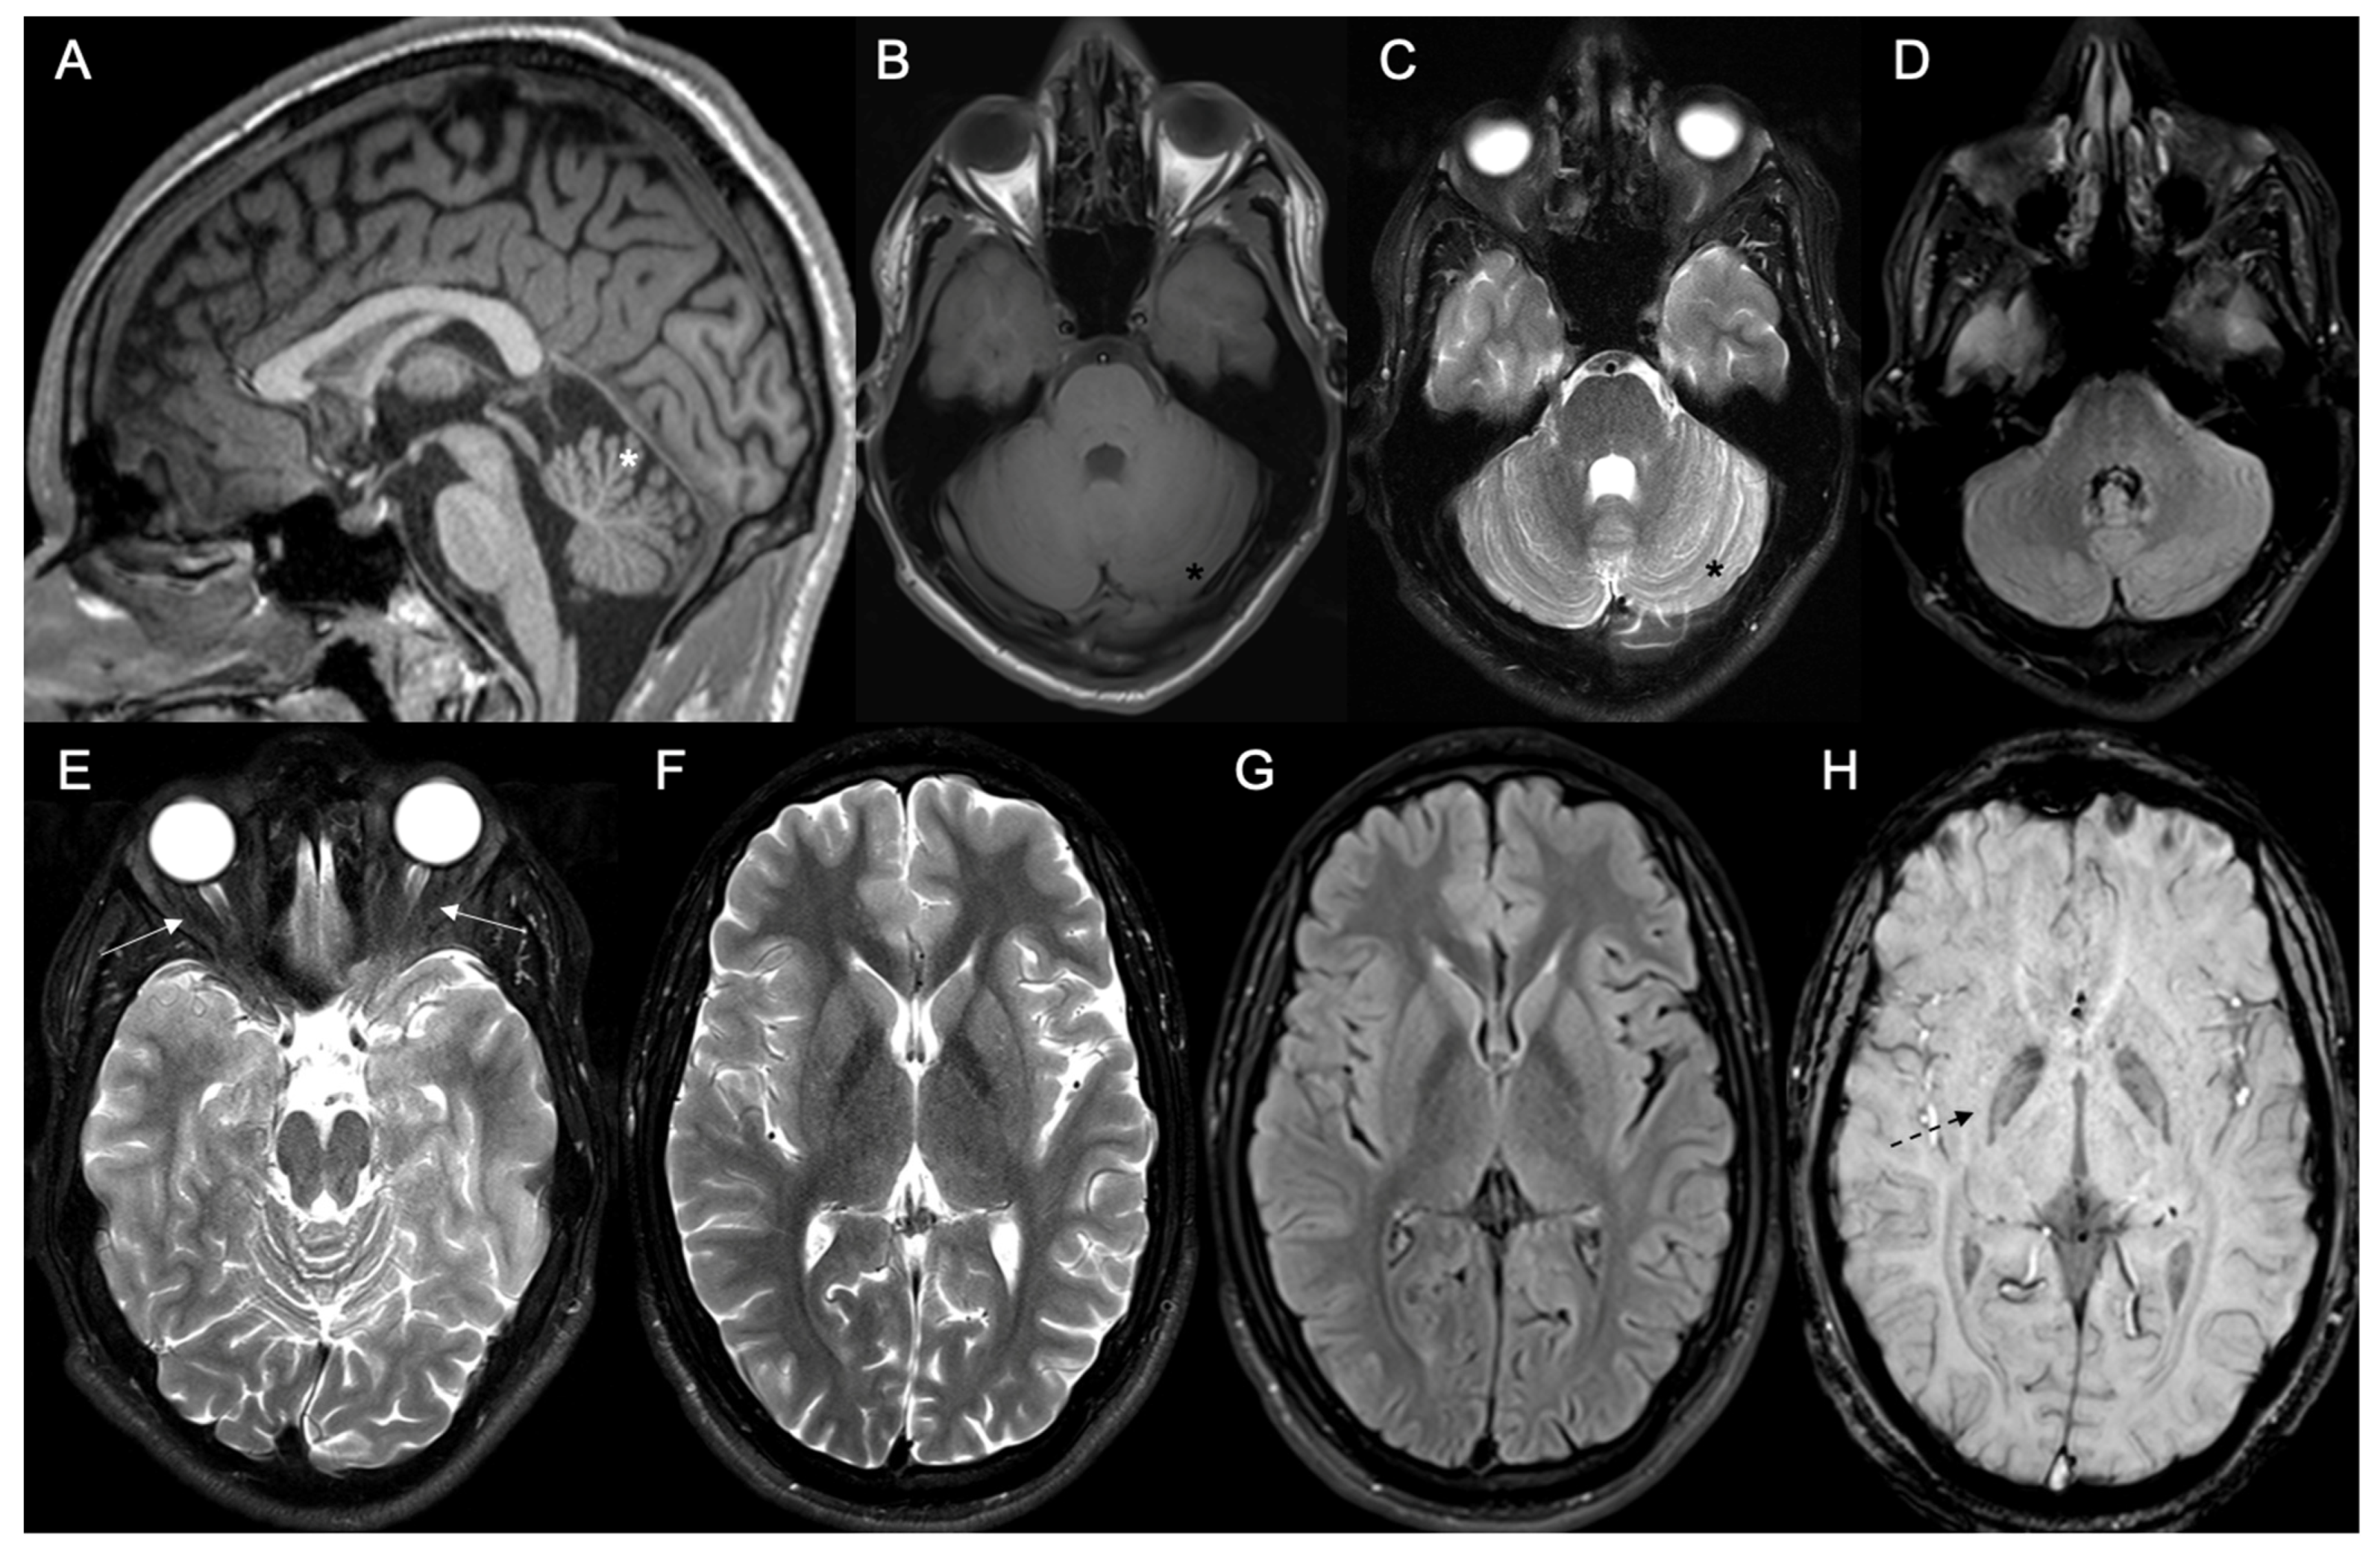

| Autosomal recessive forms (compound heterozygous or homozygous variants) | Combined Oxidative Phosphorylation Deficiency type 13 (COXPD13) (MIM #614932) | Infancy onset; rapidly progressive and severe, then nonprogressive after | Consanguinity; positive history in recurrence/variants inside the catalytic core and active site of the protein—affects multimerization and destabilizes the mutated protein | ++/++ | Myopathy, axial hypotonia, dysphagia; sensory neuropathy; axonal and demyelinating sensory neuropathy; autonomic neuropathy | ++/optic atrophy, macular pigmentary changes; nystagmus, strabismus, cataracts; chorioretinal defects | Dystonia, choreoathetosis, dyskinesia; myoclonus | Neurological regression (more marked in epileptic encephalopathy forms); global developmental delay/Cerebellar atrophy, leukodystrophy (including cystic leukodystrophy and hypomyelination), thin corpus callosum; Leigh syndrome-like pattern (caudate head, putamen); optic tract atrophy; possible lactate peak on MR spectroscopy | Scoliosis/Gastroparesis; constipation; Gastroesophageal reflux |

| Autosomal dominant form or sporadic cases (heterozygous variants) | Spinocerebellar Ataxia type 25 (SCA25) (MIM #608703) | Childhood or juvenile onset; progressive | Positive family history, despite some sporadic cases; incomplete penetrance/splicing and nonsense variants with premature stop codon | +++/+++ | Sensory neuropathy; absent tendon reflexes; axonal sensory neuropathy (ganglionopathy) | +/Strabismus; ophthalmoparesis; gaze-evoked nystagmus; slow saccadic pursuit; optic atrophy; late-onset diplopia | Facial tics; facial myokymia; dystonia; late-onset head tremor | Cognitive decline; intellectual disability (minor)/normal, cerebellar atrophy | Pes cavus, scoliosis/Gastroparesis; constipation; urinary urgency or incontinence |